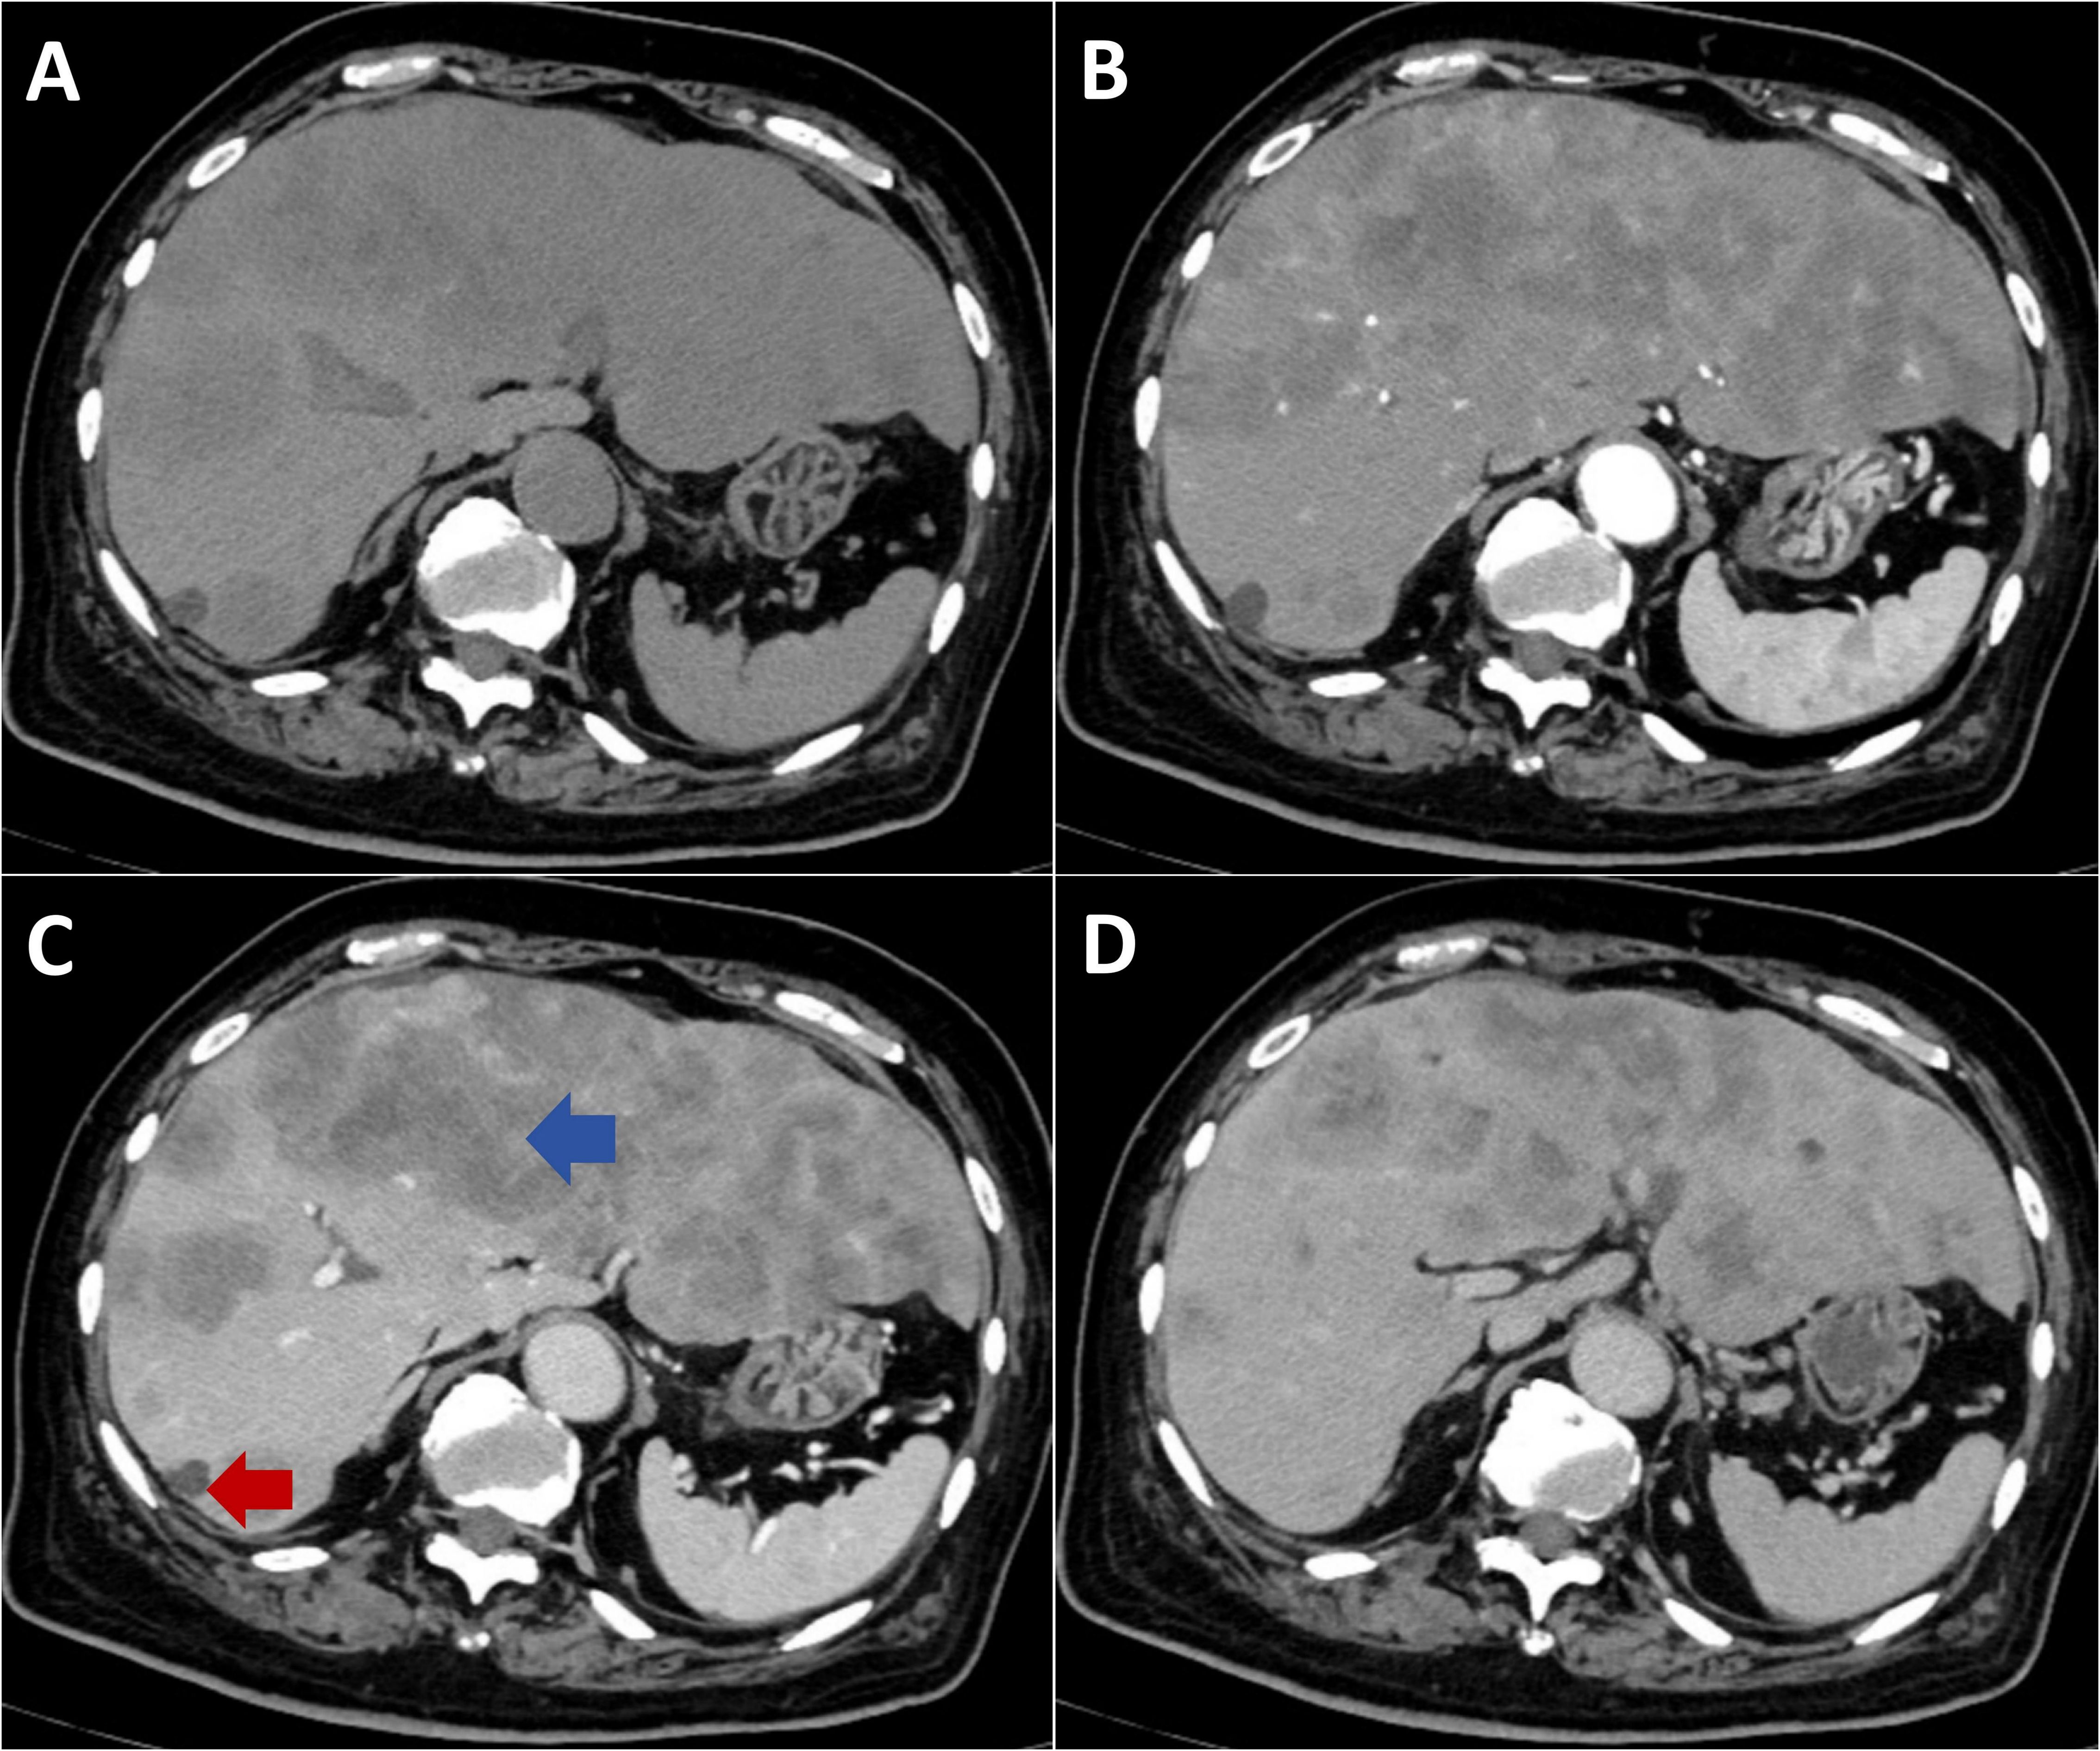

Background: Tumor lysis syndrome (TLS), characterized by electrolyte imbalances and acute kidney injury, predominantly occurs following cytotoxic chemotherapy in hematologic malignancies. Spontaneous TLS (STLS) in solid tumors remains rare. This report describes STLS induced by a diagnostic liver biopsy and reviews the literature on procedure-associated TLS. Case Presentation: An 84-year-old male presented with extensive hepatic metastases and markedly elevated tumor markers. Ultrasound-guided percutaneous liver biopsy confirmed the diagnosis of metastatic adenocarcinoma. Within 24 hours post-procedure, the patient developed acute respiratory failure, anuria, severe metabolic acidosis (pH 7.23), hyperkalemia (5.5 mmol/L), acute kidney injury (creatinine 299 μmol/L), hyperuricemia (716 μmol/L), and elevated lactate dehydrogenase (3953 U/L), fulfilling the diagnostic criteria for TLS. Concurrent hemothorax occurred. Continuous renal replacement therapy (CRRT) achieved rapid correction of metabolic derangements, with parameters returning to normal within seven days. Conclusion: Diagnostic liver biopsy can induce STLS in patients with high-burden solid tumors. Our systematic analysis reveals that minimally invasive procedures may precipitate TLS, emphasizing the importance of prophylactic measures, early recognition, and immediate CRRT initiation for optimal outcomes.